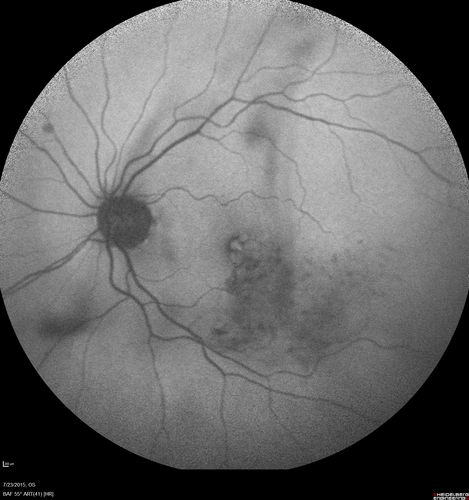

Branch Retinal Vein Occlusion

84 year old man - 2 months vision loss - VA 20/40 - 20/20 with one injection of Eylea

BRVO - dry after one anti-VEGF injection